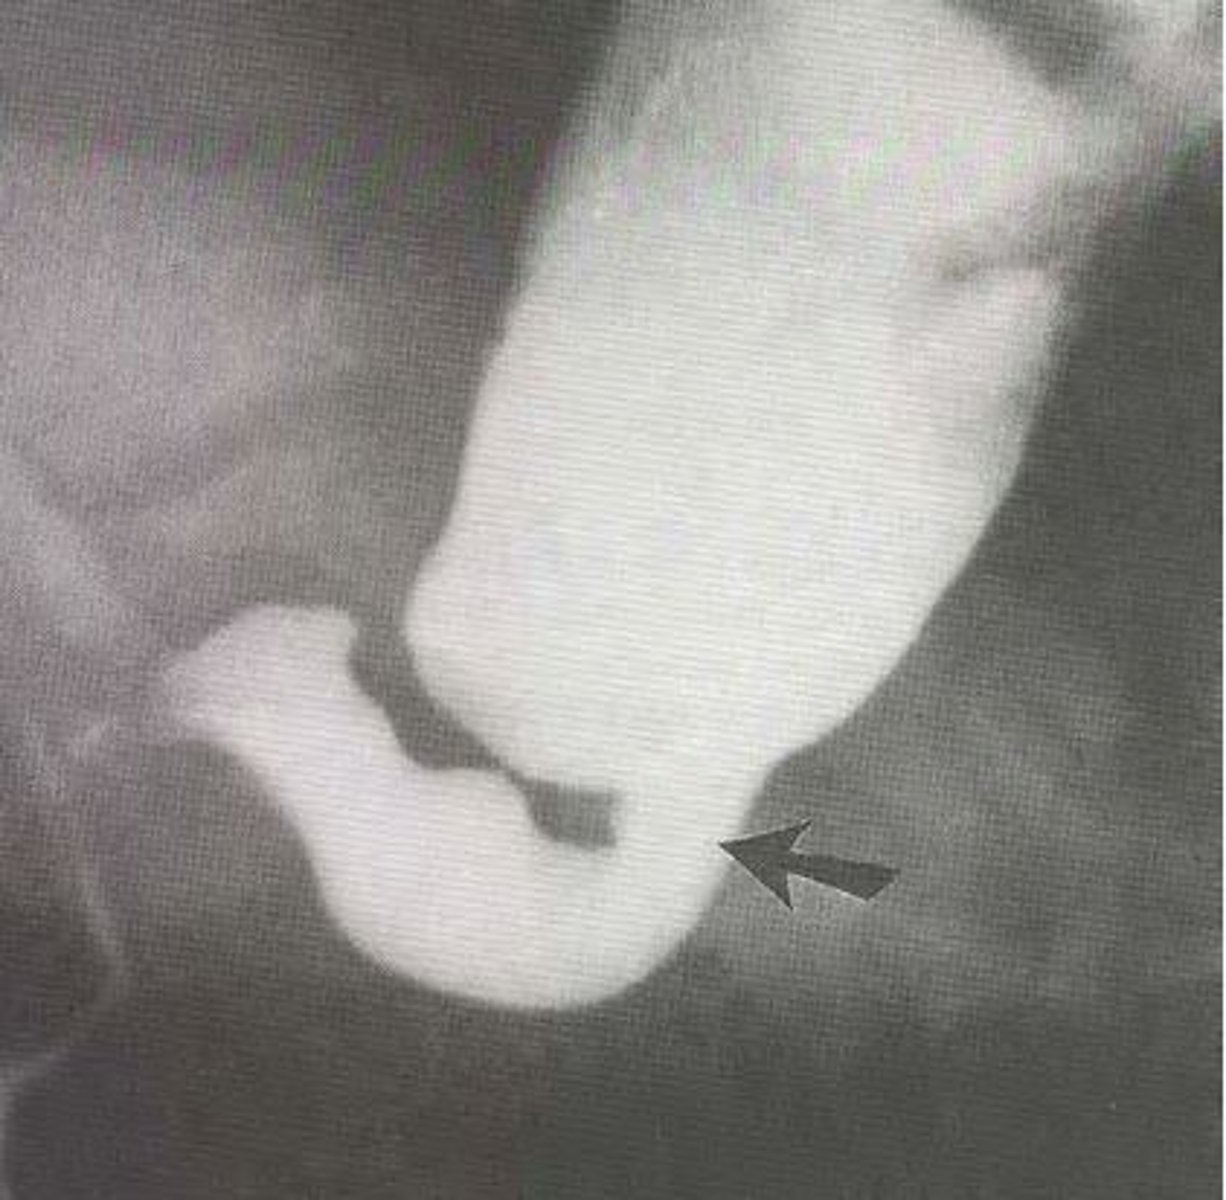

What is best initial & best overall test to diagnose hypertrophic pyloric stenosis? What will be seen?

Initial: abdominal US

Best: upper GI contrast series - string/apple core sign